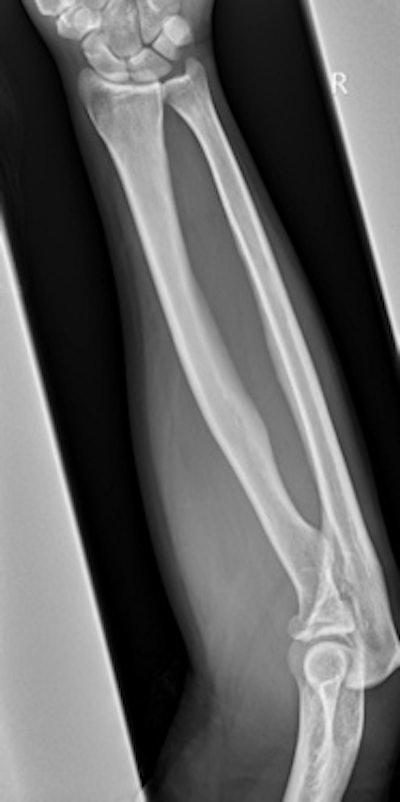

"Approximately 250 persons attend the emergency department per year with various hurling-related injuries, mostly young adults, particularly during the peak season and school matches. Hand, wrist, and upper limb injuries are the commonest," noted Dr. Nagabathula Ramesh, from the department of radiology at Midland Regional Hospital in Portlaoise, Republic of Ireland.

The most common cause of injuries is when a player is tackled by another player, and the injuries range from simple bruising and abrasions to severe dislocations and multiple system trauma. Upper extremity trauma tends to be more common in hurling, particularly the hand and the wrist, while orbital and facial are common in both types of sports, Ramesh explained.